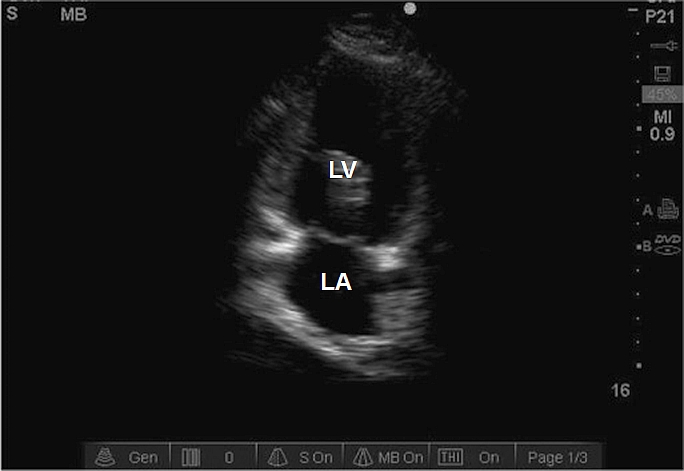

Case 7-3. Apical Four-chamber View

Video 7-3A. While the septum is centrally orientated, the left ventricle is foreshortened. This was the best view that could obtained in this obese patient on ventilatory support, continuous hemofiltration, and high-dose pressors. The intensivist faces major obstacles in obtaining the apical views related to patient habitus, supine position, respiratory translational artifact, and ICU equipment that blocks good scanning position. In this case, there is moderate right ventricular (RV) enlargement with normal RV free wall function. At times, the intra-atrial septum bows into the left atrium, suggesting elevation of right atrial pressures. The subcostal long-axis view would be obligatory alternative view to examine RV wall thickness and septal kinetics.

Video 7-3B. Mild mitral regurgitation (MR) by color Doppler, but with a wall jet pattern. A MR wall jet is known to result in an underestimate of the severity of MR. This mandates examination of multiple views and, if indicated, advanced methods for determining the severity of the MR. In this case, the wall jet pattern was seen in multiple views, but the MR was determined to be moderate in severity by vena contracta measurement.

Video 7-3C. Mild to moderate tricuspid regurgitation. The jet is well oriented for measurement of the TR velocity. Other views showed a similar degree of TR.